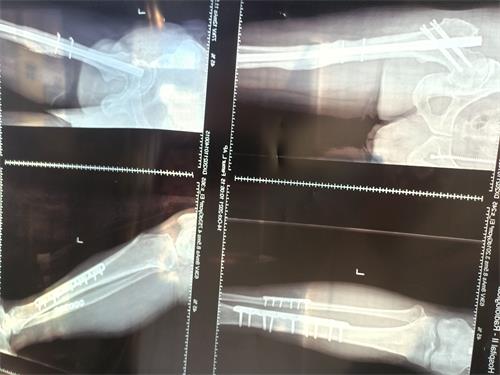

医院检验发现,我的右侧第二肋骨前支骨折伴右侧气胸,肺压缩15%,左侧第六肋骨骨折;左侧股骨、左侧胫腓骨中下段骨折,断端重叠错位并成角,面部、眼睛多处划伤。护士用冰袋把我的左腿裹着,然后像高射炮那样架在病床上,病床周围摆满了各种仪器,头上、手上、胸前到处是各种传感器电线。我的整个左腿从臀部到脚后跟好几处骨折,而且脚踝骨上面一段是粉碎性骨折,一堆骨渣子已经无法修复。

主治医生建议,一是从我身体其他部位取些骨头去修补,二是花钱购买骨头修补。我妻子选择购买骨头修补。手术前,医院要我妻子在手术风险告知书上签字,上面写了一大堆手术可能发生的危险,其中一句话写的是术后双腿的长短可能不一致,也就是说今后可能成为瘸子。经过几天的各种医疗检验,X拍片、CT、B超、脑电图、心电图、彩超、血液化验等等,经过九个小时手术后,住院三十天后出院了。